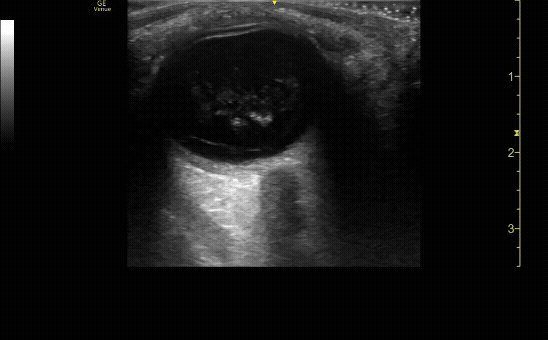

Vitreous hemorrhage displaying “washing machine” sign.

c/o Rayyan Kadi, MD